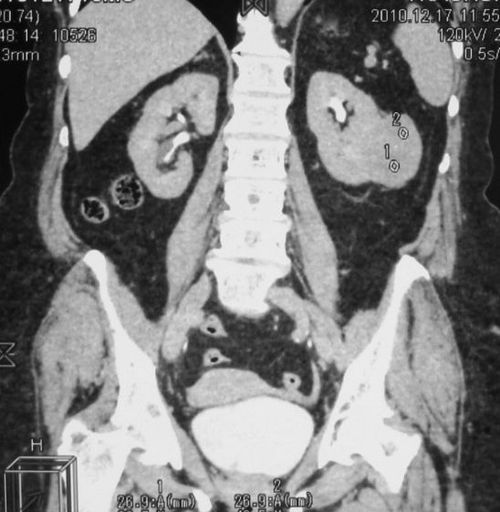

Опухоль левой почки